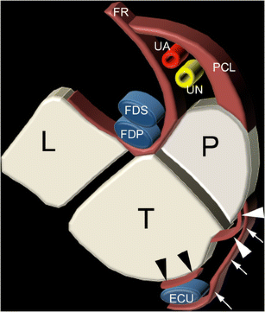

Fig. 3